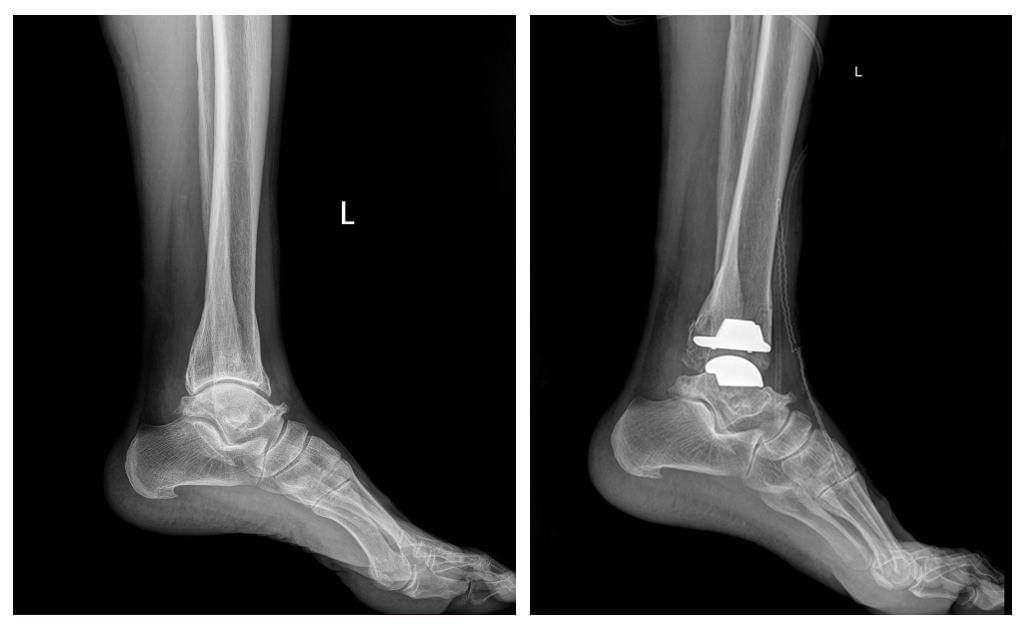

ГССҮТ-ийн Насанд хүрэгсдийн мэс заслын тасгийн их эмч Ш.Баасансүрэнгээр ахлуулсан, тус тасгийн эрхлэгч Б.Баатаржав, Г.Бадамгарав нарын мэс заслын баг бүрэлдэхүүн шагайн үений хүнд хэлбэрийн артроз өөрчлөлтийн үед хиймэл үе суулгах мэс заслыг хийж, орчин үеийн дэвшилтэт мэс засал эмчилгээг тусламж үйлчилгээнд бүрэн нэвтрүүлээд байна.

Тус тасгийн хамт олон 2022 оны арваннэгдүгээр сард БНСУ-ын “Йонсей Гунвоо” эмнэлгийн захирал Eui Hyun Park болон бусад эмч, мэргэжилтнүүдтэй хамтран Монголд анх удаа шагайн хиймэл үе солих мэс заслыг хийсэн бөгөөд 2023 оны арванхоёрдугаар сараас эхлэн энэхүү мэс засал эмчилгээг бие даан амжилттай хийж буй юм.

Шагайн үений хүнд хэлбэрийн артроз өөрчлөлтийн үед хиймэл үе суулгах мэс заслыг Монголд нутагшуулснаар энэ төрлийн шалтгаант өвчлөл, зовиураар шаналж буй иргэд үйлчлүүлэгчид олон улсын стандартыг хангасан тусламж үйлчилгээг эх орондоо, бага зардлаар илүү хялбар, чанар хүртээмжтэй авах, амьдралын чанараа дээшлүүлэх зэрэг таатай боломж бүрдэж байна.